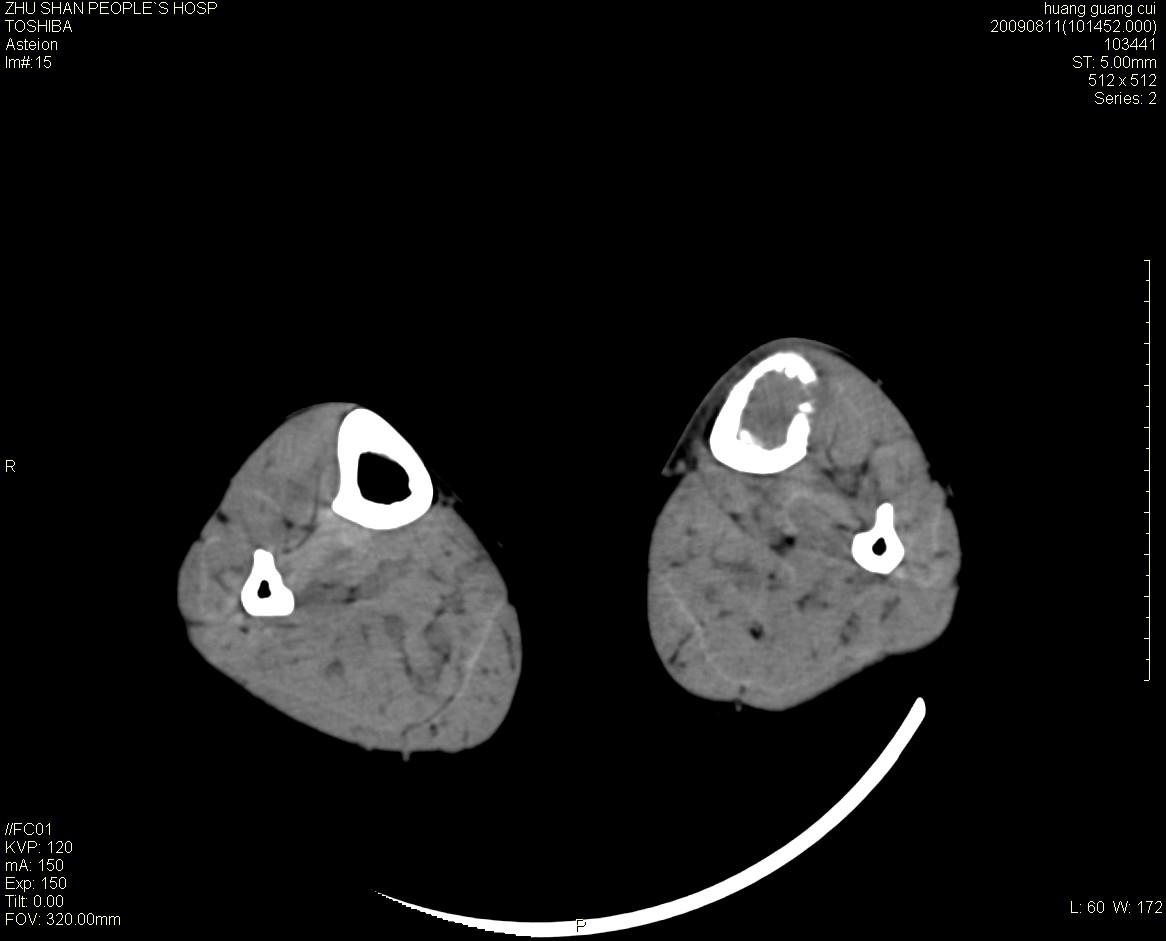

女性 56岁 左胫骨中断肿痛2月余。转移瘤or尤文氏肉瘤?

左侧胫骨中段骨皮质溶骨性破坏,髓腔内外见软组织肿块,无明显钙化及成骨,定位相显示病变周围“筛孔样”改变,定性恶性无疑,原发或转移均有可能,倾向于骨纤维肉瘤可能性大,转移瘤不排除。膝关节以下骨转移很少,且要有原发灶支持,尤文氏肉瘤年龄太大不支持。